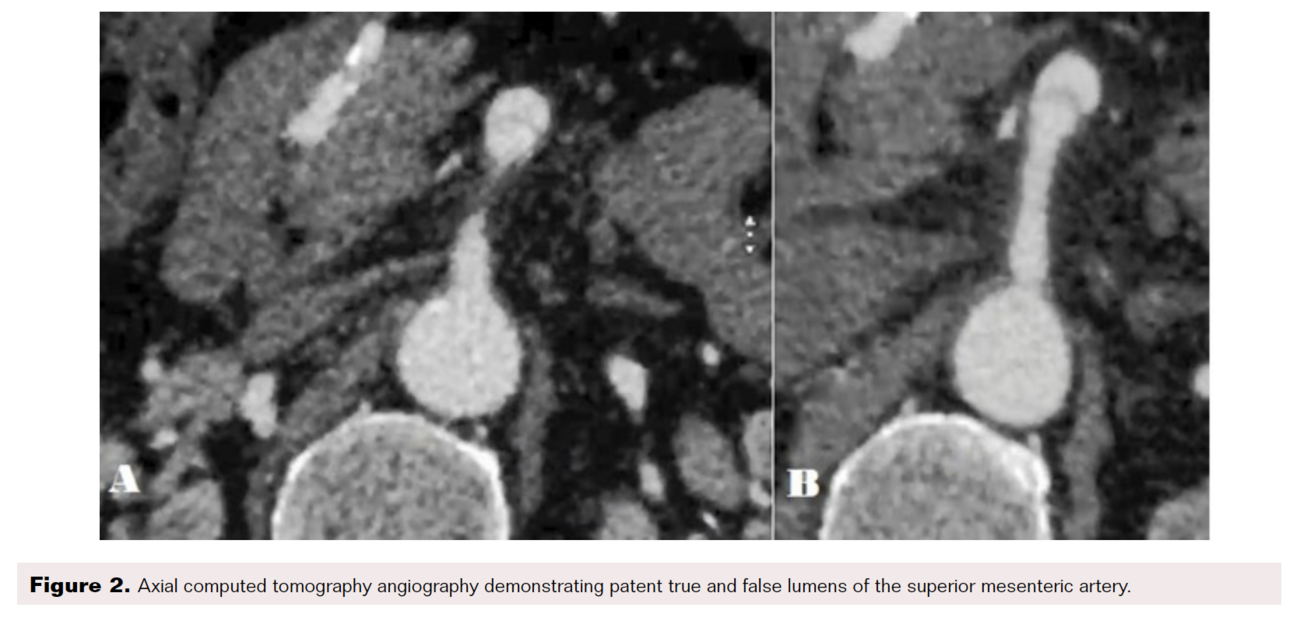

Over the next 36 hours, the patient’s abdominal pain persisted; however, he did not develop any leukocytosis, lactic acidosis, tachycardia, or fever. Due to the patient’s refractory pain, despite objective evidence of bowel ischemia, we performed a repeat CTA, which did not reveal any new findings. A decision was made to proceed with angiography to better define the dynamics of his SMA dissection and potentially intervene on an endovascular basis. Although CTA demonstrated a patent true lumen, on selective mesenteric angiography there was dynamic obstruction of the distal SMA from the thrombosed false lumen (Figure 3). Given the potential risks of an endovascular approach and the need to deploy a long stent to treat the dissected SMA, a decision was made to proceed with open surgical repair.